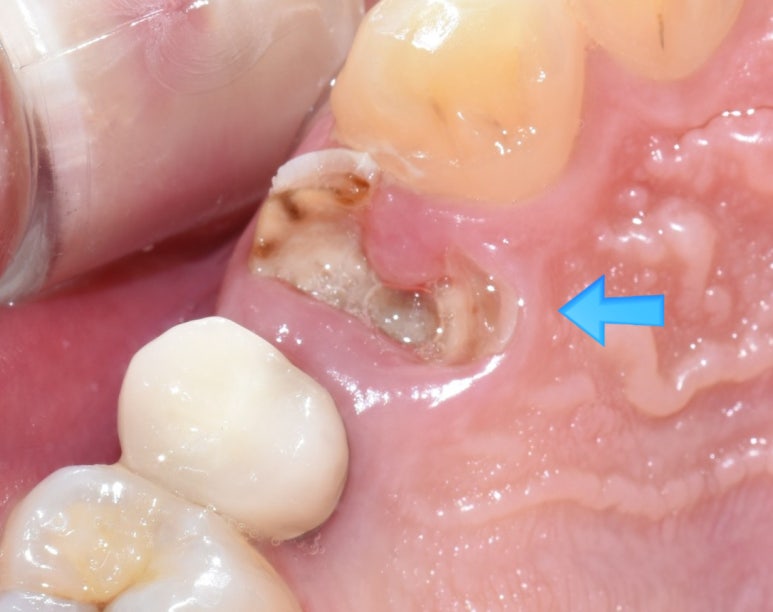

같은 치아의 전후 사진입니다.

위 사진을 보면 왼쪽사진에서 겉에서 보이는 충치가 있고

겉에서는 보이지 않고 엑스레이 상에서만 보이는 충치가 있었는데

실제로 치아를 파보면 같은 깊이를 팠을 때 겉에서 보이던 충치의 깊이보다

겉에서 안보이던 충치가 훨씬 더 깊고 상태가 심각함을 볼 수 있습니다.